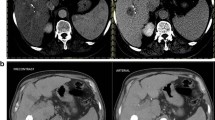

MRI tumor segmentation at baseline and 3 months after treatment

TTV and ETV on CE MRI both at baseline and 3 months after treatment were approximated by summarizing the volumes of a maximum of three dominant lesions in 58 patients (Table 2). The inter-reader agreeability of our unidirectional and volumetric MRI measurements as measured with the Pearson correlation coefficient (PCC) statistic varied between 0.93 and 0.99 (Supplement 3) which is in line with results from previous studies [22,23,24]. The measurements for target lesion TTV at baseline correlated significantly with total tumor volume assessment performed routinely before radioembolization with a PCC of 0.88 (p < 0.001). After transformation with the natural logarithm, baseline TTV and ETV followed a log-normal distribution. The non-logarithmic ETV/TTV ratio showed a pronounced bimodal distribution with frequency peaks between 10 and 30% and above 80% relative arterial tumor vascularization (Fig. 3). ROC analysis and Youden’s J statistic revealed an ETV/TTV threshold of 50% to be most suitable to stratify patients in two significantly different (p < 0.001) groups in terms of ETV change as assessed with the Mann–Whitney U test. Patients with a baseline ETV/TTV ratio greater than 50% (25/58 patients) showed a median reduction in ETV by 51% and less variability with an IQR of 58%. Patients with a ratio less than 50% (33/58 patients) had a median increase in ETV of 58% with an IQR of 200% (Fig. 4). Apart from a higher proportion of BCLC C patients in the group with a baseline ETV/TTV ratio < 50% (45% of the patients vs. 20% of the patients in the ETV/TTV ≥ 50% group), the two groups did not show significant differences with respect to baseline clinical variables (Supplement 4).

Impact of relative vascularization at baseline on later decrease in enhancing tumor volumes. Line charts in A to C depict the development of enhancing tumor volume (ETV) and total tumor volume (TTV) between baseline and follow-up MRI for patients with low tumor vascularization (ETV/TTV < 50% in baseline MRI), high tumor vascularization (ETV/TTV > 50% in baseline MRI), and the whole cohort. The change of median ETV over time in both subgroups is compared with boxplots in D